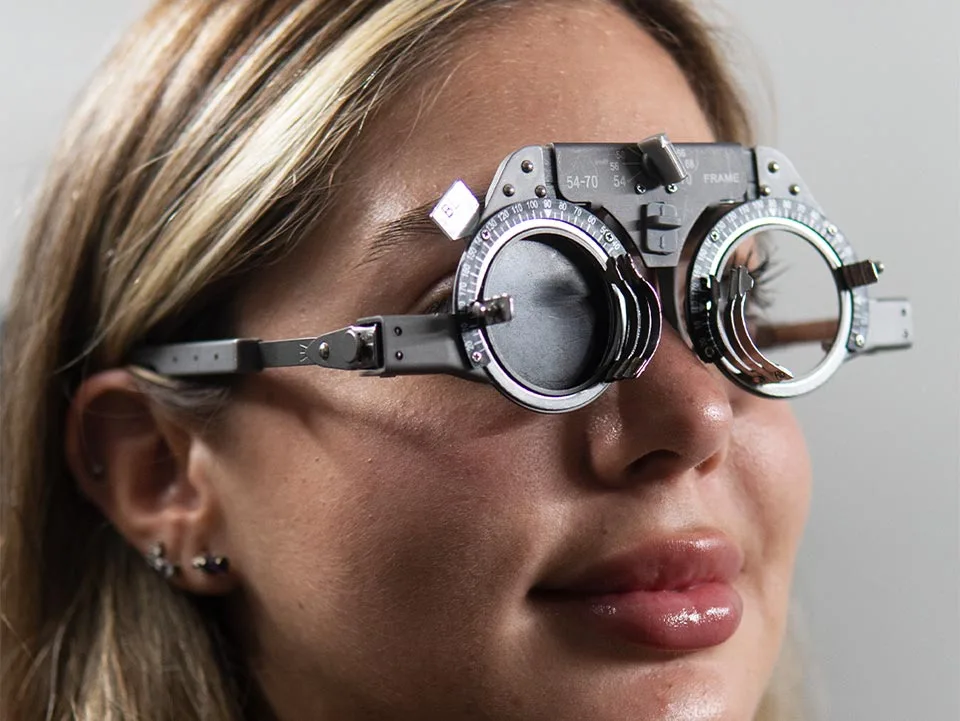

Optometría

Cirugía Refractiva

- Astigmatismo

- Cirugía Refractiva

- Hipermetropía

- Miopía

- Presbicia